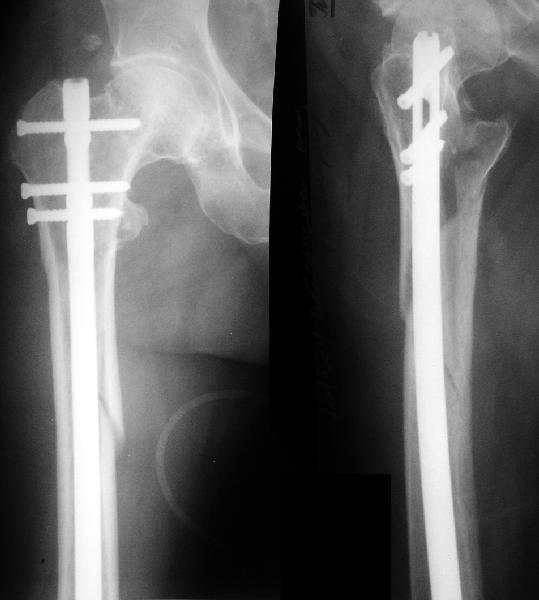

Вчера оперировали - винты удалены через 1 прокол. Затем выполнили закрытый интрамедуллярный остеосинтез без расверливания бесканальным гвоздем 13 мм (реконструкционного для нее не нашлось). Гвоздь заперт статически - в проксимальный отломок 3 винта 6 мм, в дистальный - 1.

Учитывая варус сросшейся шейки, постарался вальгизировать проксимальный отломок, насколько гвоздь позволил. Результат в приложении. Картина перелома видна лучше, чем на начальных снимках.

The screws were removed through a stab wound. Then a closed insertion of an unreamed solid nail 13 mm was performed and the nail statically locked - 3 screws 6 mm in the proximal fragment and 1 in the distal.

Considering varus of the healed neck i tried to get some valgus to the proximal fragment as the nail allowed. The result attached. The fracture pattern can be seen better than in the initial films.